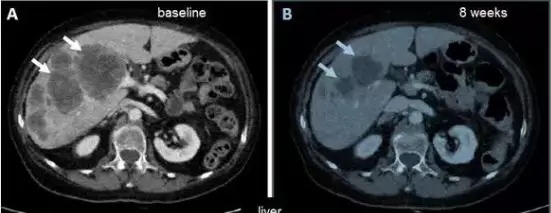

每周口服1600mg / m 2恩曲替尼一周一次,连续4天(即4天/ 3天休息),每28天连续三周。治疗八周后,病灶明显缩小。

肝转移瘤明显萎缩